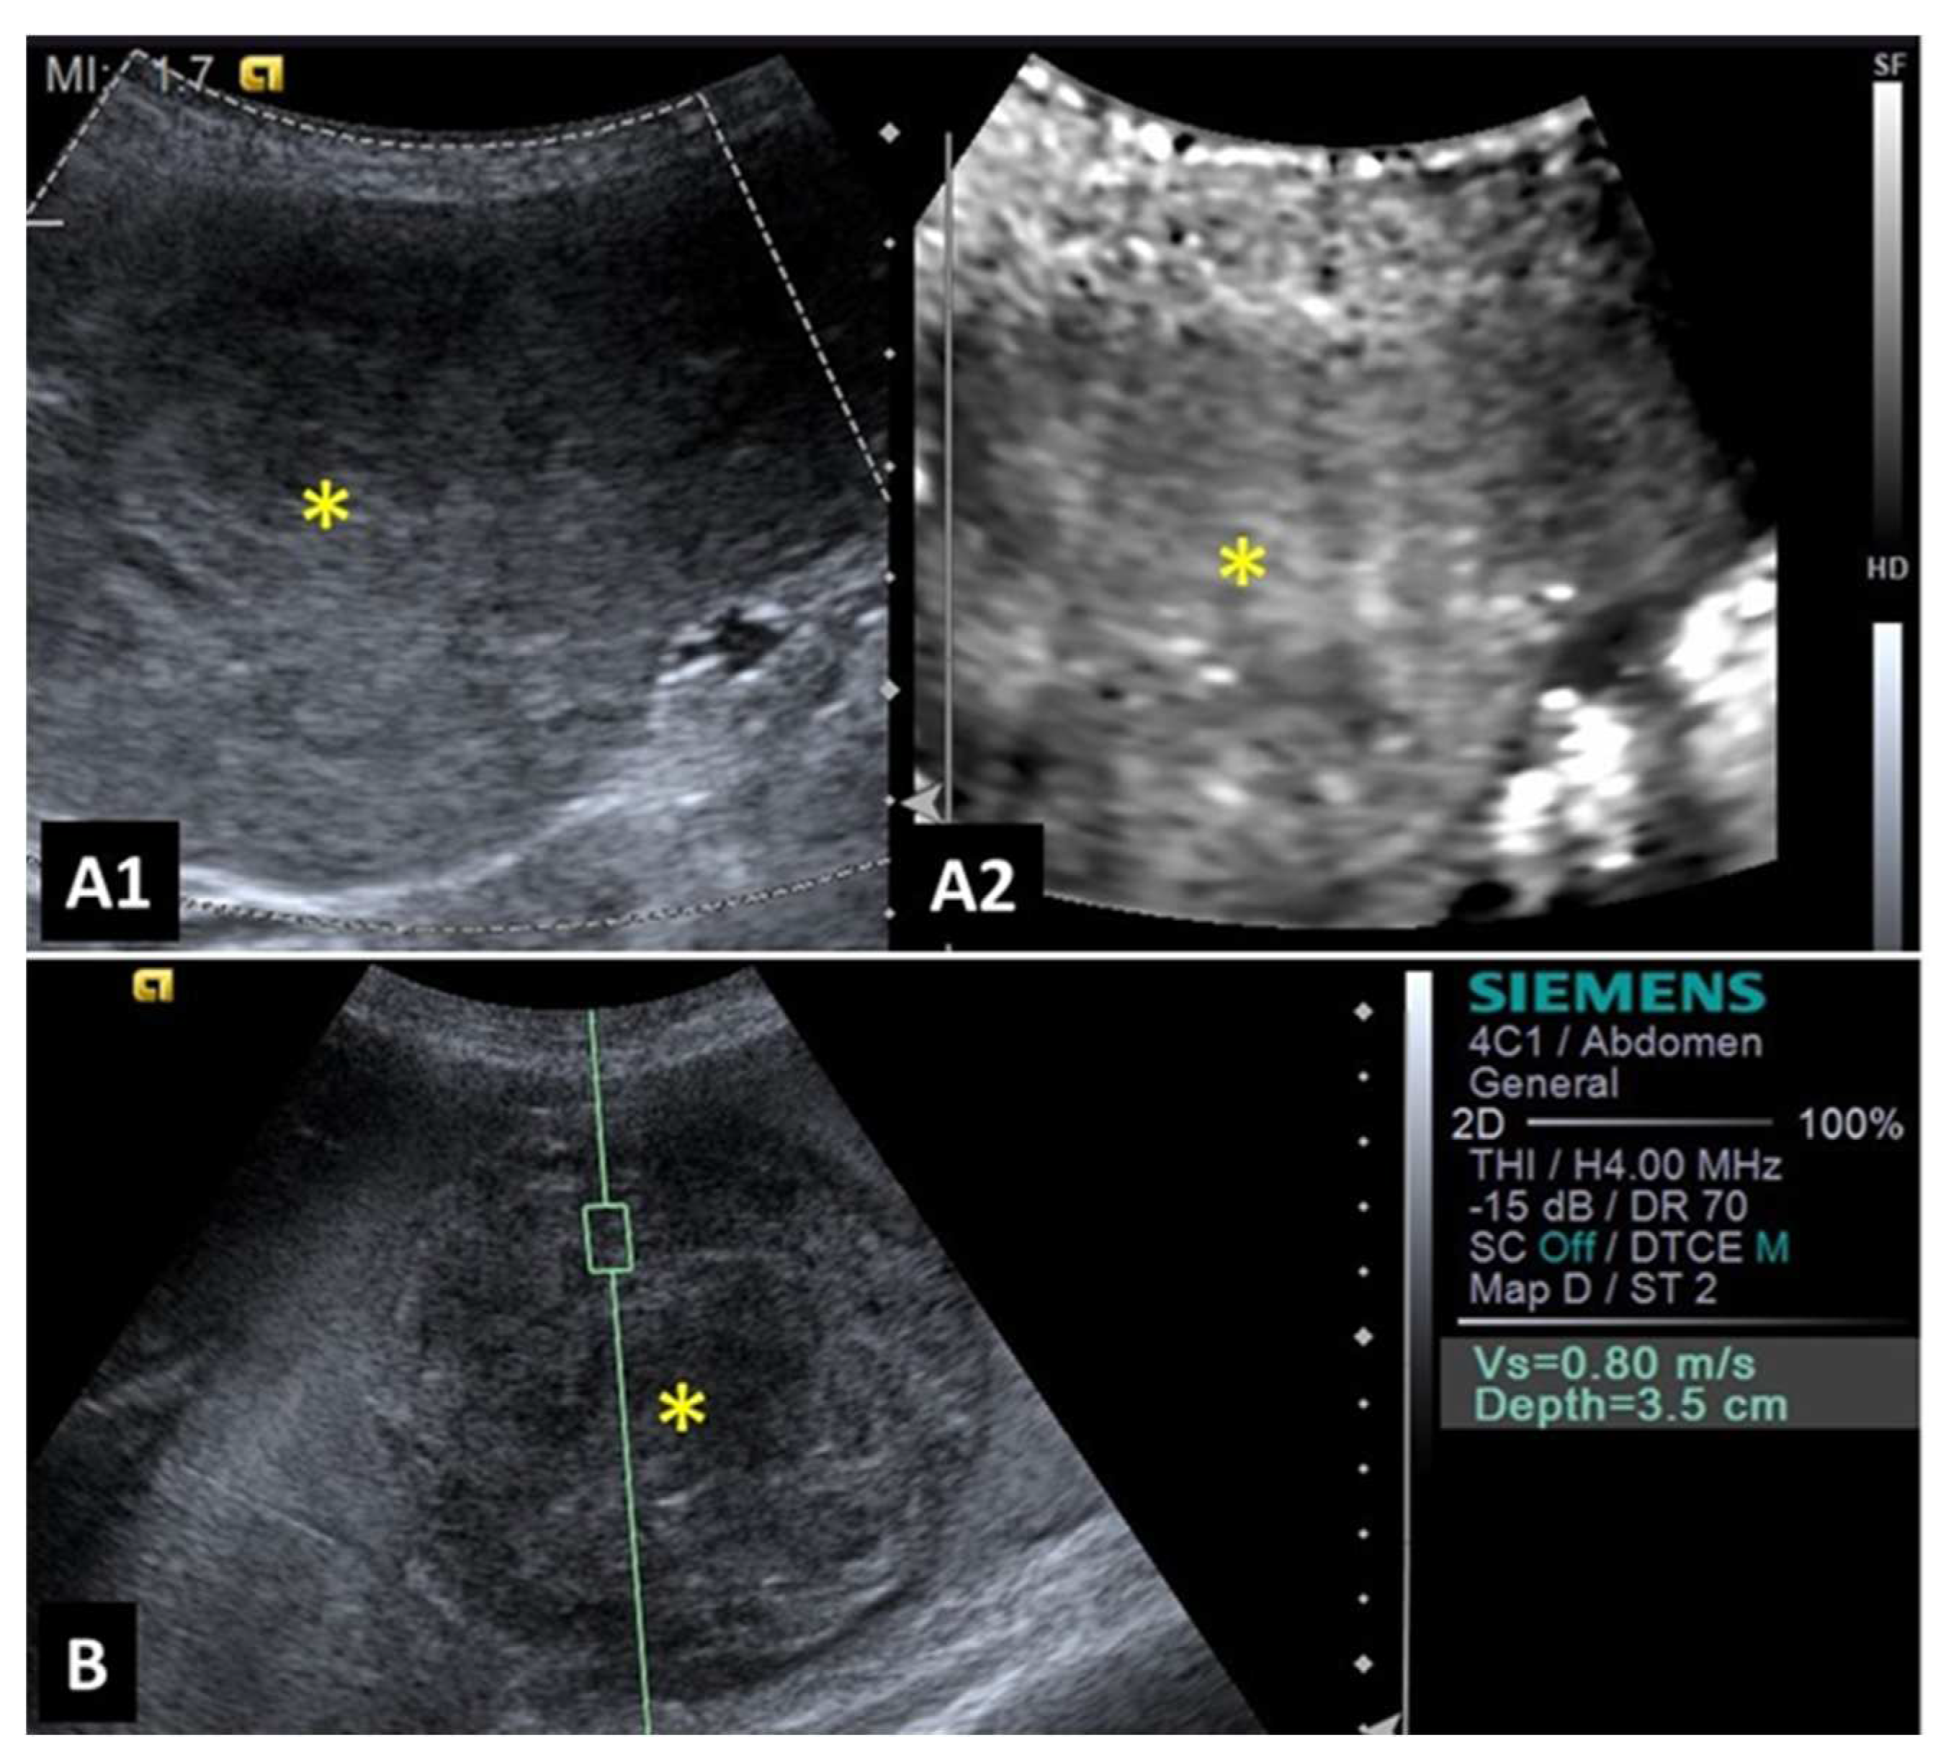

Strain elastography was used to differentiate malignant and benign hypoechoic splenic lesions smaller than 4 cm in width based on the elasticity index and stiffness value. Malignant lesions presented an elasticity rate equal to or greater than 1.5 and a stiffness value higher than 70% [28]. These authors explained that stiffness value is calculated as the percentage of the lesion that is encoded as rigid, whereas the elasticity index can be calculated by the ratio between an area of normal parenchyma and the corresponding area of the entire lesion, considering the assessment of areas of the same size and depth.

A study evaluating 37 spleens of patients with splenic nodules observed that malignant nodules exhibited higher shear wave velocity compared to benign ones, indicating that malignant lesions are stiffer [27]. This characteristic demonstrated that shear wave elastography was 97% accurate to detect malignant splenic nodules (considered superior to advanced imaging methods such as magnetic resonance imaging). The authors reported that a shear wave velocity greater than 2.6 m/s was indicative of malignancy in splenic lesions with 95% sensitivity, 100% specificity, and an accuracy of 97%. Examples of elastographic images of splenic nodules can be seen in Figure 1 and Figure 2.

Figure 1. Image of a benign splenic lesion (hematoma) in a dog: (A) B-mode of the splenic lesion with mixed and heterogeneous echogenicity; (B) ARFI elastography of the hematoma, demonstrating shades and shear velocity values indicative of decreased rigidity and benignity.